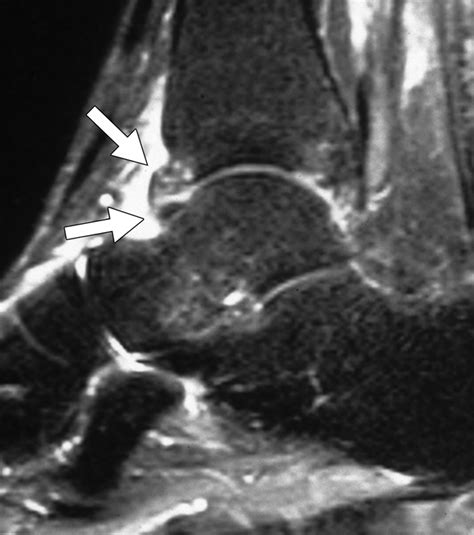

Magnetic Resonance Imaging (MRI) Offers detailed images of the bone marrow and surrounding tissues, making it the gold standard for diagnosing bone marrow edema.